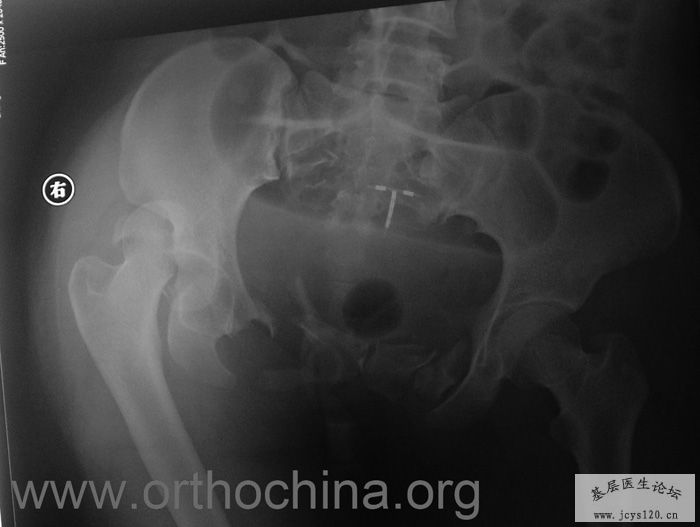

患者,女,28岁,车祸中骨盆轧伤后疼痛功能障碍1小时。查体:休克外貌,烦躁不安。头颈胸腹无异常,脊柱无异常,两下肢血供及感觉正常。骨盆挤压分离试验阳性。阴道、尿道、直肠、腹内脏器无损伤。住院后抗休克、骨牵引及对症治疗1周后,行前后联合入路手术。股骨头骨折复位后用可吸收螺钉固定,骶髂关节、髋臼前后柱、对侧耻骨上下支用骨盆重建钛板固定,术中出血1200ML,手术时间8小时。部分图片如下: